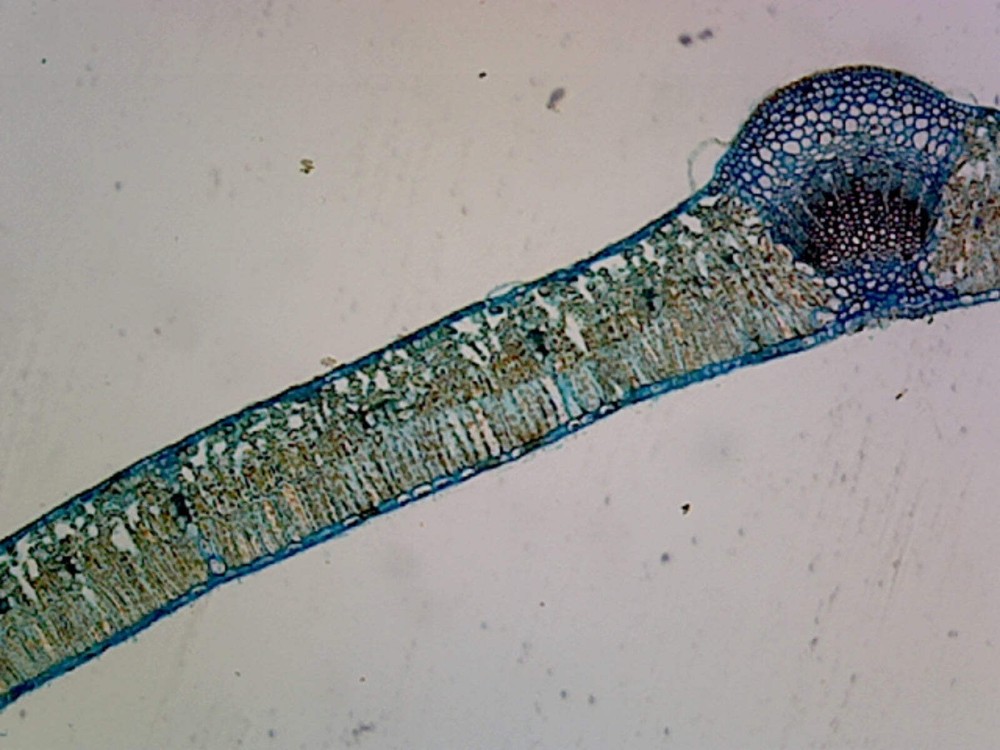

Check the listing for details. Mcmaster Method Microscope Slide - FEC (Fecal Egg Count) or Worm Count, Double C. Color: Blue, Condition: New. Listed at 32.00 USD. FECRT (Fecal Egg Count Reduction Test) Reference Guide Included. Fecal Egg Count Reduction Test (FECRT) Reference Guide Included. Designed for a quick, easy, accurate fecal egg counting process. Make evidenced based deworming protocols by doing your a Fecal Egg Count Reduction Test using the standard, original Mcmaster Egg count slide.